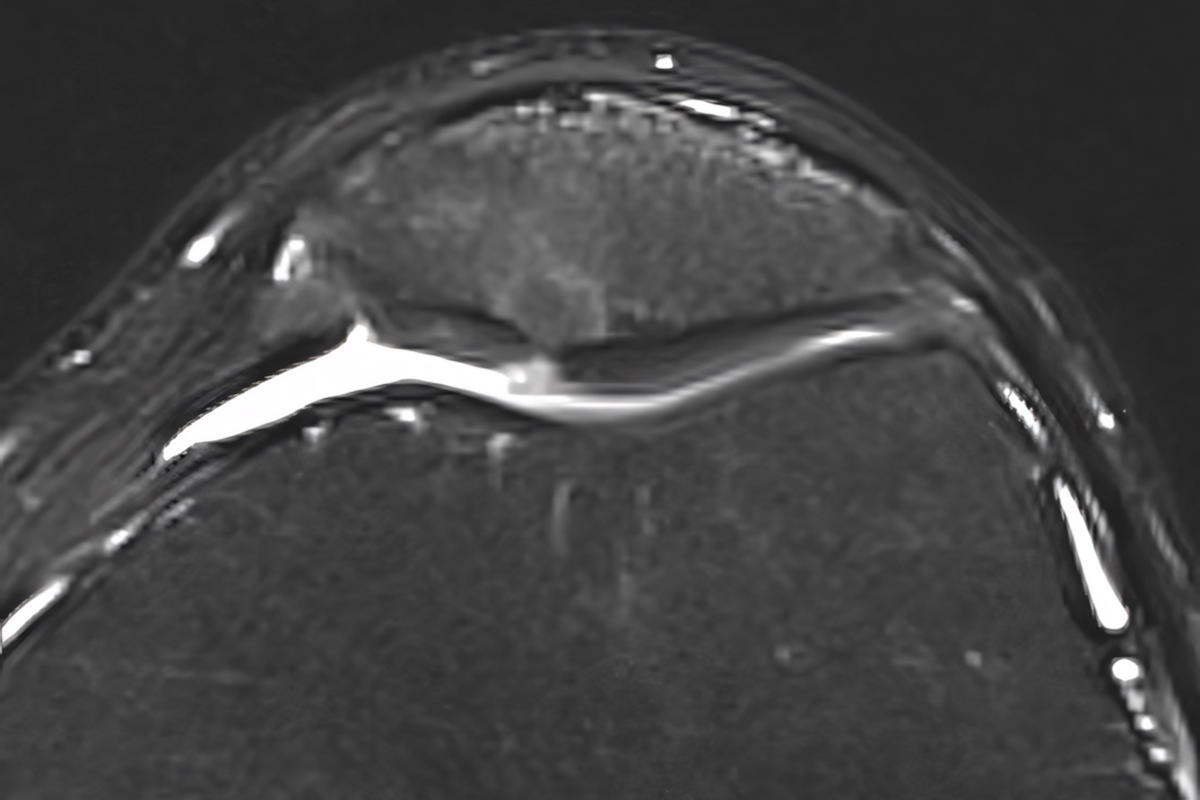

Μαγνητική τομογραφία (MRI) για εκτίμηση της βλάβης του χόνδρου

Η MRI είναι ιδιαίτερα χρήσιμη για την αξιολόγηση του βαθμού εκφύλισης.